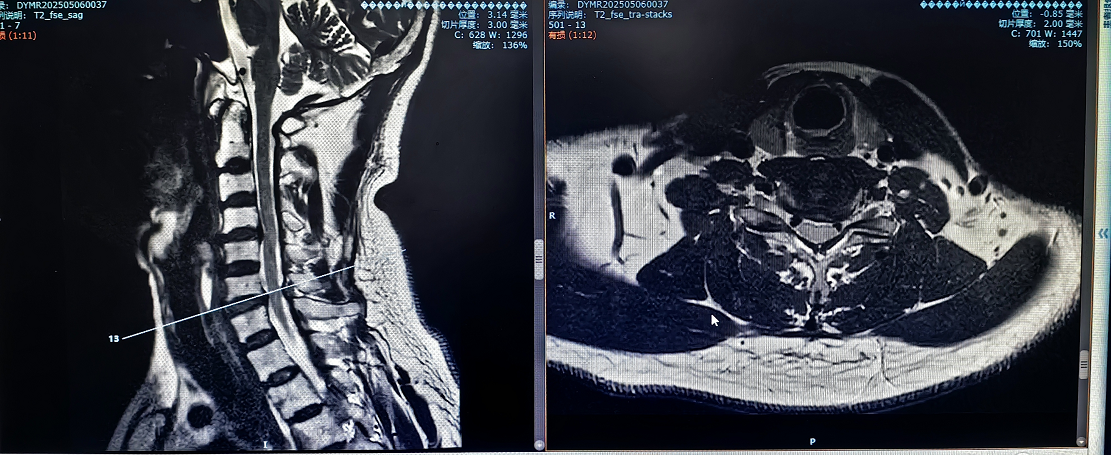

患者因"頭痛、雙上肢麻木伴下肢乏力1月"入院,此前長期保守治療效果不佳,癥狀持續(xù)加重并出現(xiàn)行走不穩(wěn)。經(jīng)多學科聯(lián)合會診,團隊決定采用國際先進的零切跡cage融合術。手術歷時2小時,出血量僅10ml,術后患者即刻感到頸部及肢體癥狀顯著緩解,術后三天即可下床活動,微創(chuàng)切口(3—4厘米)及快速康復效果獲家屬高度贊譽。

1.采用小型化、低切跡的融合器(cage),切口僅3—4厘米,術中對軟組織剝離少,有效降低血管、神經(jīng)損傷風險;

2.其零切跡設計貼合頸椎生理曲度,減少對食管刺激,避免術后吞咽不適;